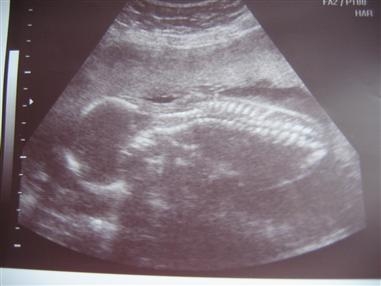

Back from my 20 Wk Ultrasound....

I'm resizing pics as I type...but I'm happy to report we are right on target with how far along I am and how big she is. They think she weighs about 10 ounces.

We reconfirmed that she is a girl and SO NOT SHY about it

She sucked her thumb, had the hiccups, and even flipped from face up to face down. We saw all sorts of different parts of her body which was amazing.

Image Attachment(s):

Your pictures always come out so perfect...like you can see every little bone. Incredible!!